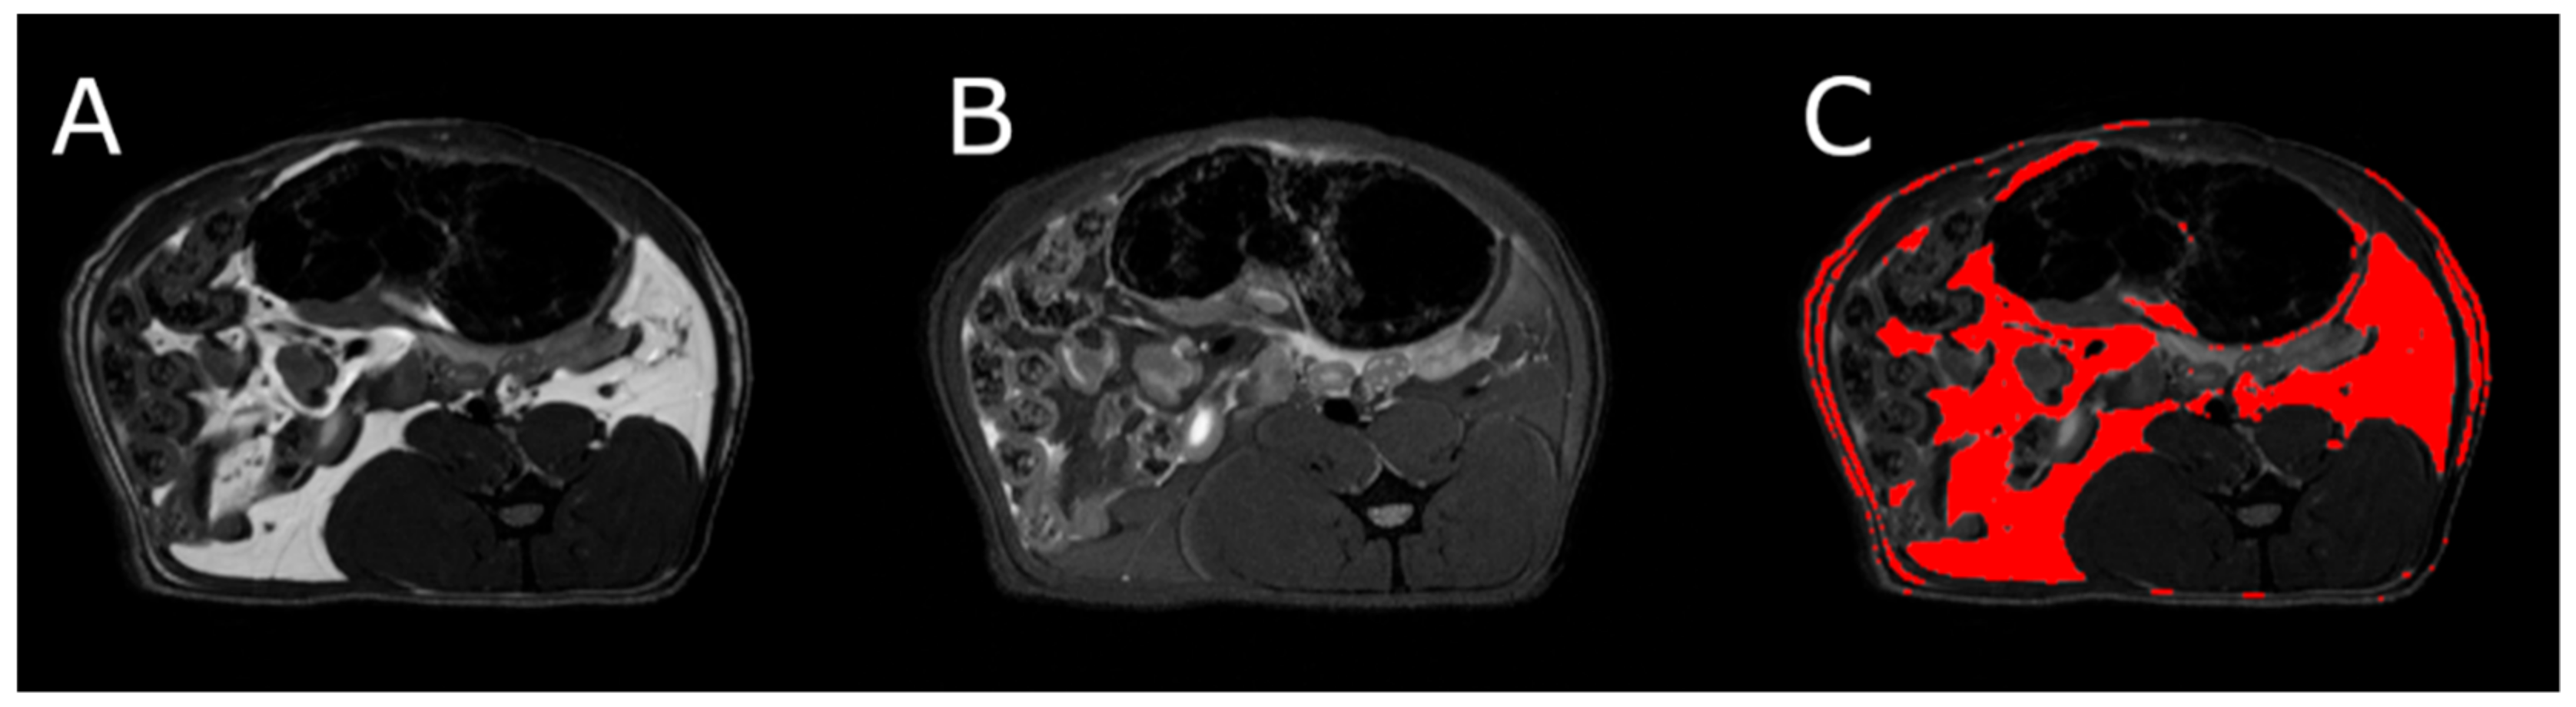

3.5. Body Composition

MRI measurements showed a significant reduction in the adipose tissue volume of ABA rats compared with controls (Figure 5). The mean visceral body fat reduction in the ABA rats reached 58.9% on day 6 of the experiment (Figure 6).

Figure 5.

MRI scan of female healthy rat, the cross section of the abdomen at L4 level. (A) RARE image without fat suppression; (B) fsupRARE image with fat suppression; (C) segmentation result—adipose tissue marked in red.